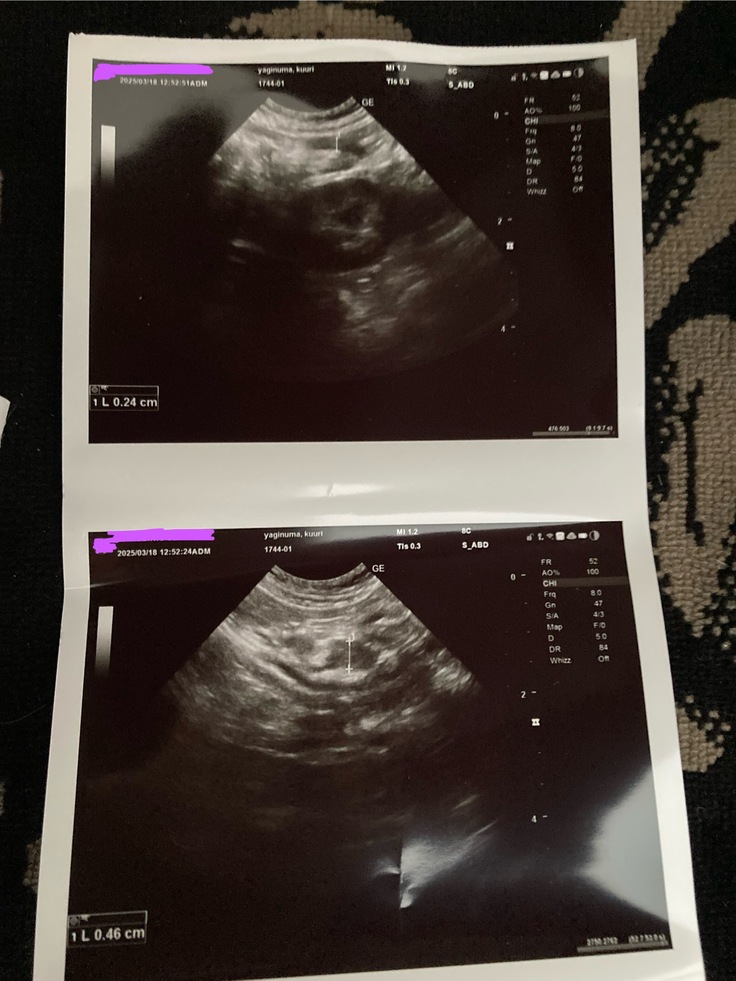

先日の検査で腸のリンパは腫れたままでした。

獣医師の説明では、もしかしたら薬の副作用で腫れていて、投与が終われば小さくなるのではないかとのコトでした。